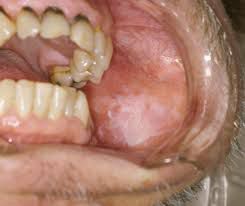

Leukoplakia , thickened, white patches form on your gums, the insides of your cheeks, the bottom of your mouth and, sometimes, your tongue. These patches can't be scraped off. Doctors don't know what causes leukoplakia but consider chronic irritation from tobacco — whether smoked, dipped or chewed — to be the main culprit in its development.